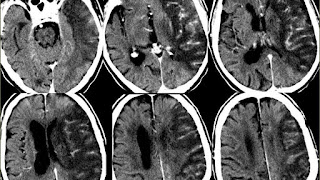

Brain ischemia (a.k.a. cerebral ischemia, cerebrovascular ischemia) is a condition in which there is insufficient blood flow to the brain to meet metabolic demand. This leads to poor oxygen supply or cerebral hypoxia and thus to the death of brain tissue or cerebral infarction / ischemic stroke. It is a sub-type of stroke along with subarachnoid hemorrhage and intracerebral hemorrhage.

There are two types of ischemia: focal ischemia, which is confined to a specific region of the brain; and global ischemia, which encompasses wide areas of brain tissue.

Multiple cerebral ischemic events may lead to subcortical ischemic depression, also known as vascular depression. This condition is most commonly seen in elderly depressed patients. Late onset depression is increasingly seen as a distinct sub-type of depression, and can be detected with an MRI.